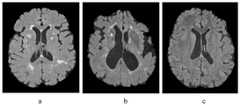

图2标准化前训练样本和测试样本的横向切片;a.训练样本,b.测试样本#1,c.测试样本#2;Figure 2. Transverse slices of training samples and test samples before normalization; a. training sample, b. testing

从测试样本集中随机选取两个样本作为测试样本。图2是分别从训练样本、测试样本#1和测试样本#2的MRI数据中选取的位于横切120/256位置的切片图像。图3是三个样本的直方图曲线,从图3可以看出,测试样本2的波峰对应的强度值明显低训练样本,测试样本1的波峰对应的强度值接近训练样本,这也是为什么图2中的测试样本1的切片亮度与训练样本接近,测试样本2的切片亮度相对训练样本偏暗的原因。接下来对三个样本进行图像强度的标准化统一处理。Two samples are randomly selected from the test sample set as test samples. Figure 2 is a slice image selected from the MRI data of the training sample,